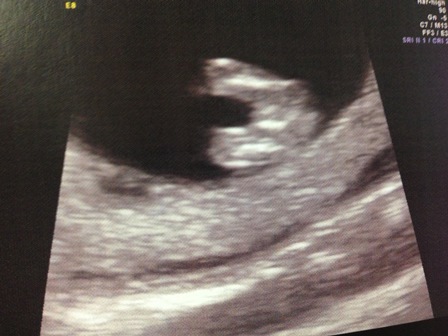

Ok so I have to apologise, this bub is a mover and groover and would barely stay still so I dont think I've got any good pictures of a nub.. was hoping a few of you might have an opinion on what you see though? Any feedback is much appreciated!! Attachment 15352Attachment 15353

I've got one side profile and one potty shot :) This was a scan at 13 weeks exactly :)